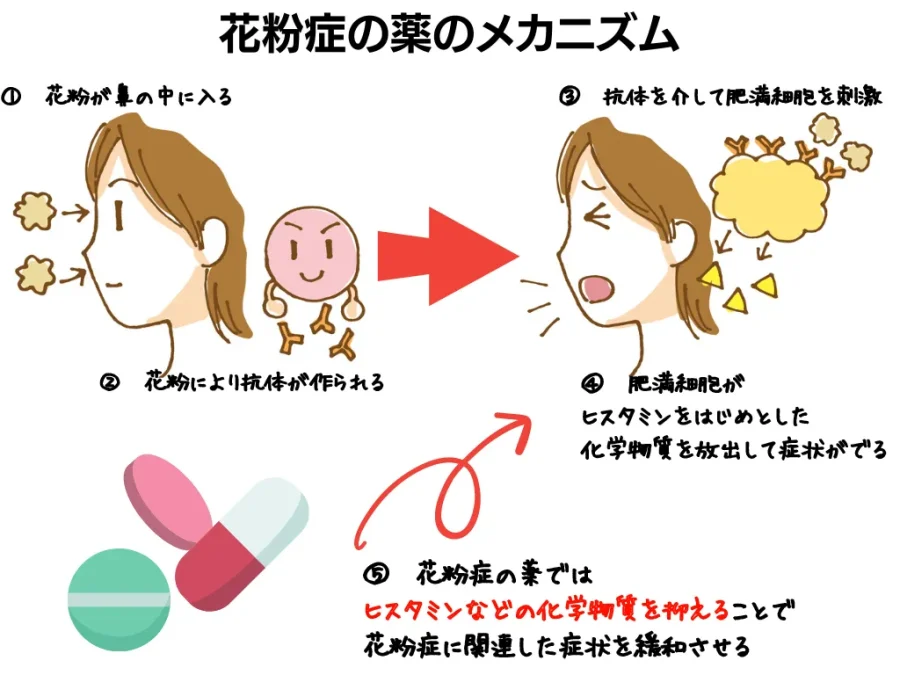

2025年 花粉症かな?と思った方へ 〜症状や薬を解説〜アレグラFX。

花粉症の薬について 比較・強さ・眠くならないひまわり医院 内科・皮膚科。

花粉症の薬について 比較・強さ・眠くならないひまわり医院 内科・皮膚科。